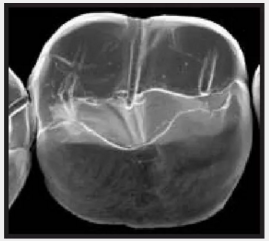

復(fù)合樹脂在即刻充填后,觀察其在電子顯微鏡下的掃描圖像,本次研究選擇了9種具有代表性的復(fù)合樹脂材料。

1.png

Clearfil Majesty Kuraray America 可樂麗